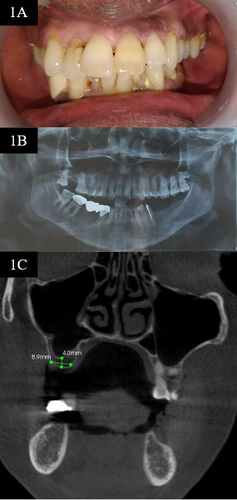

Background: Tooth extraction is generally accompanied by bone remodeling and pneumatization of the maxillary sinus in the posterior region of the maxilla, which can result in a reduction in the height and width of the bone and compromise the placement of the implant. However, this anatomic deficiency can be restored via maxillary sinus elevation. Among the various surgical methods used, the indirect sinus floor elevation technique is relatively less invasive and less complex.

Aim: Herein, we present the case of a 58-year-old partially edentulous female who underwent rehabilitation of the right maxillary molar region using the indirect sinus floor elevation technique. The hydraulic lift system was used followed by immediate implant placement.

Relevance for patients: This technique incorporates the advantages of both the lateral wall and crestal approaches for sinus elevation and is associated with a lower incidence of sinus membrane perforation and minimum bone loss.